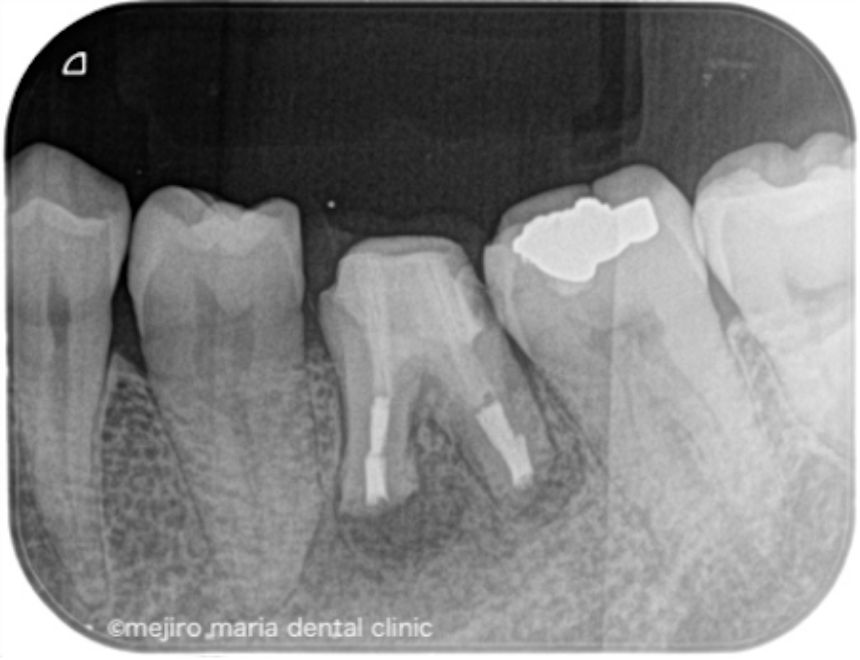

治療後の様子

術後3ヶ月の経過観察では、歯肉の腫れや噛んだときの違和感、痛みは消失し予後良好と判断しました。引き続き最終補綴処置(被せ物)の製作を行い2年間の経過観察に移行することとなりました。

今回の症例は長期間病状を放置してしまった結果、根管の外に歯石が形成され、根管治療のみで治癒させることができず、次いで歯根端切除術を行うことで治癒に導いた症例です。

根尖孔外(根の外)に感染源がある場合根管内部の洗浄をいくら行ったとしても感染を除去することは出来ません。その為、根の治療の訓練を受けた専門医が根管治療を施しても改善が認められない場合は速やかに歯根端切除術へ移行することが望ましいと考えられます。